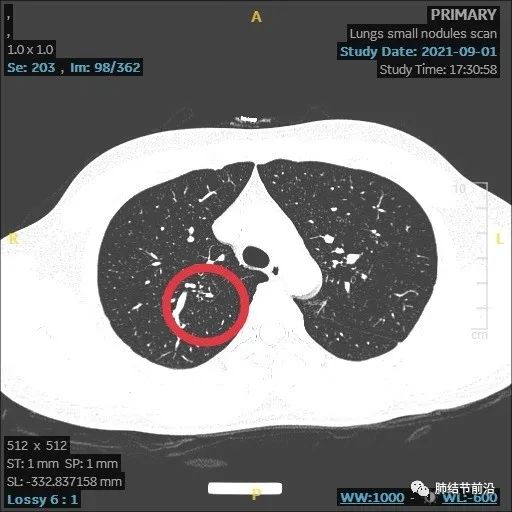

结节变大,形态变化,出现多中心微小结节堆积形态,而之前实性8mm结节却不见了。

虽然结节变大,但这个时候反而安心了,大的8mm实性结节消失,变成多中心微小结节。这样不符合肺癌的发展规律,考虑炎症性结节。因为恶性结节,只会实性成分扩大。

本病例显示了炎症性结节的发展过程,由8mm实性结节,变成了14mm的多中心堆积结节,后面又自行吸收。炎症为何种病菌感染,无法肯定,该结节也有结核可能。

多中心堆积结节,多考虑炎症肉芽肿,如果病灶中随访慢慢变实性,再考虑为腺癌。应注意影像特点,避免误切。